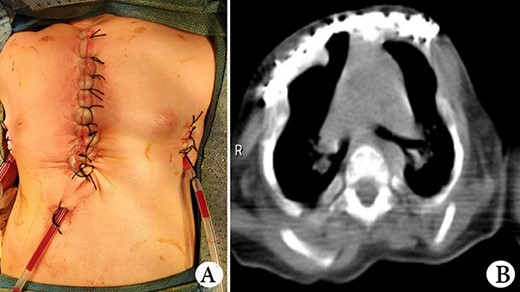

The patient was a female infant born at term with no family history. After birth, the patient developed cyanosis and dyspnea immediately, and emergency intubation and ventilation were performed. One week later, she was weaned and oxygen was given with mask. Oxygen saturation could be maintained basically, but it would decrease when eating and crying. She was eventually diagnosed as ATD and admitted to our hospital to accept surgery four months after birth. Physical examination showed that her chest circumference was 35 cm, and her thorax was narrow and small (Fig. 1A). CT scan revealed that her thorax was deformed, the lateral chest walls were slightly sunken and the lung compression was obvious (Fig. 1B). The operation was performed under general anesthesia. Midsternotomy was made. After the two sternal halves were expanded, three steel bars were placed and fixed on the anterior surface of the sternum (Fig. 2A and B). The bars were covered with pectoralis major muscles, and the skin incision was eventually sutured (Fig. 3A). The chest circumference increased to 40 cm, and the respiratory function was significantly improved postoperatively. Mechanical ventilation was continuously used for 3 days after operation. After weaning, the mask was used for intermittent oxygen supply and stopped 35 days after operation, with the oxygen saturation maintaining above 91%. The patient was discharged 41 days postoperatively. She was followed up for 3 months. There was no hypoxia when calm, but mild hypoxia when crying, which would be relieved after quiet. CT examination 3 months after operation showed that the shape of thorax is improved (Fig. 3B).

(A) Thorax appearance after operation, and (B) CT scan image of thorax after operation.